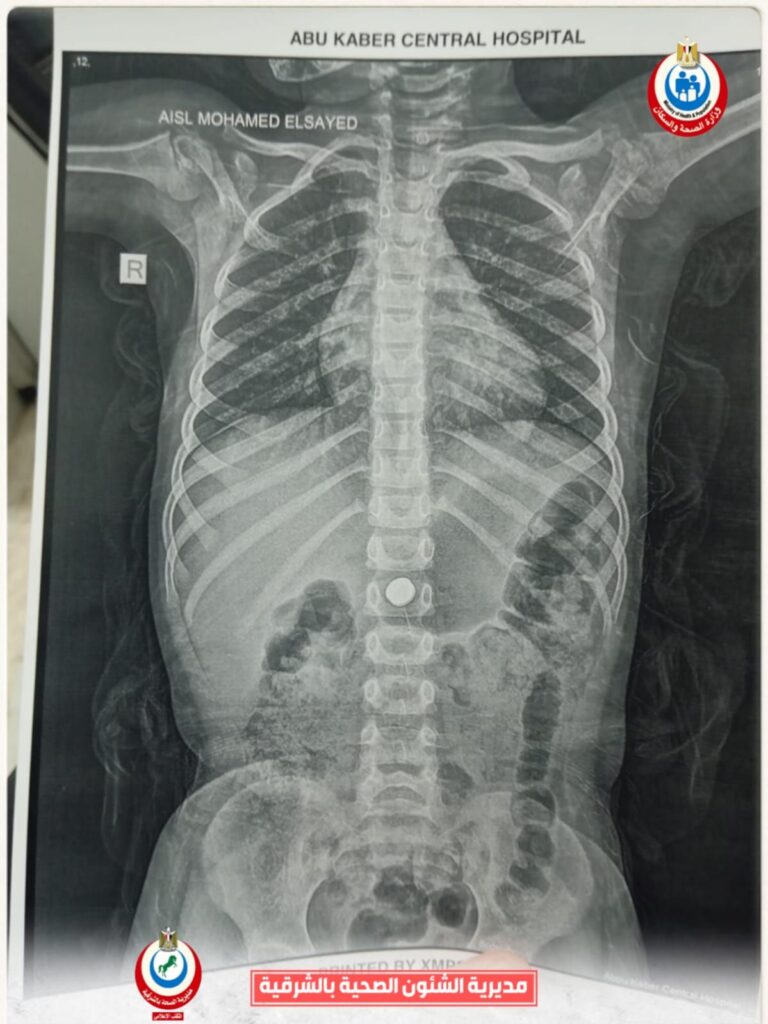

وأوضح الدكتور أحمد البيلي وكيل وزارة الصحة بالشرقية، أن الطفلة حضرت إلى قسم الاستقبال والطوارئ بالمستشفى بعد ابتلاع بطارية معدنية صغيرة، وهي من الحالات شديدة الخطورة التي قد تؤدي إلى حروق كيميائية عميقة بالمريء أو المعدة خلال وقت قصير، أو قد يصل الأمر إلى حدوث ثقوب أو نزيف حاد يهدد حياة الطفلة، نظراً لقدرة البطاريات على تفريغ شحنتها داخل الجسم خلال دقائق قليلة، مما استدعى سرعة التعامل الفوري مع الحالة وإجراء منظار ذات مهارة لها دون أي تأخير.

وأشار الأستاذ محمود عبدالفتاح مدير الإعلام والعلاقات العامة بالمديرية، إلى أنه فور استقبال الحالة، تم التنسيق الفوري من خلال مركز الخدمات الطارئة ١٣٧ بالمديرية، وتم تحويل الحالة إلى وحدة مناظير الجهاز الهضمي للأطفال، وإجراء كافة الفحوصات الطبية اللازمة لها، وإجراء منظار عاجل باستخدام التقنيات الحديثة، حيث نجح الفريق الطبي بفضل الله، في استخراج البطارية باستخدام شبكة المنظار، رغم صعوبة الحالة ووجود طعام داخل المعدة، وذلك مع الحفاظ على سلامة الأنسجة وعدم حدوث مضاعفات، وخرجت الطفلة بحالة عامة جيدة، وتحت الملاحظة الطبية للاطمئنان على استقرار حالتها.